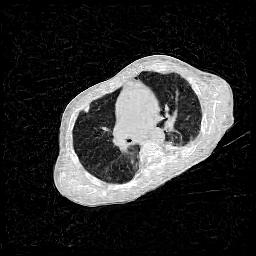

IV-F Real CT Reconstruction

To further verify the effectiveness of the RBP-DIP framework, real CT data from the Finnish Inverse Problem Society [49, 50] was used to validate our algorithm. The few-view and limited-angle reconstruction results are shown in Figure 12. Due to the lack of available training sets, pre-trained models were not included in the experiments. Different from the previous experiment, data from Finnish Inverse Problem Society is highly noisy. However, it is still evident that the RBP-DIP outperforms all other algorithms in all experiments, even under high noise and highly ill-posed conditions.